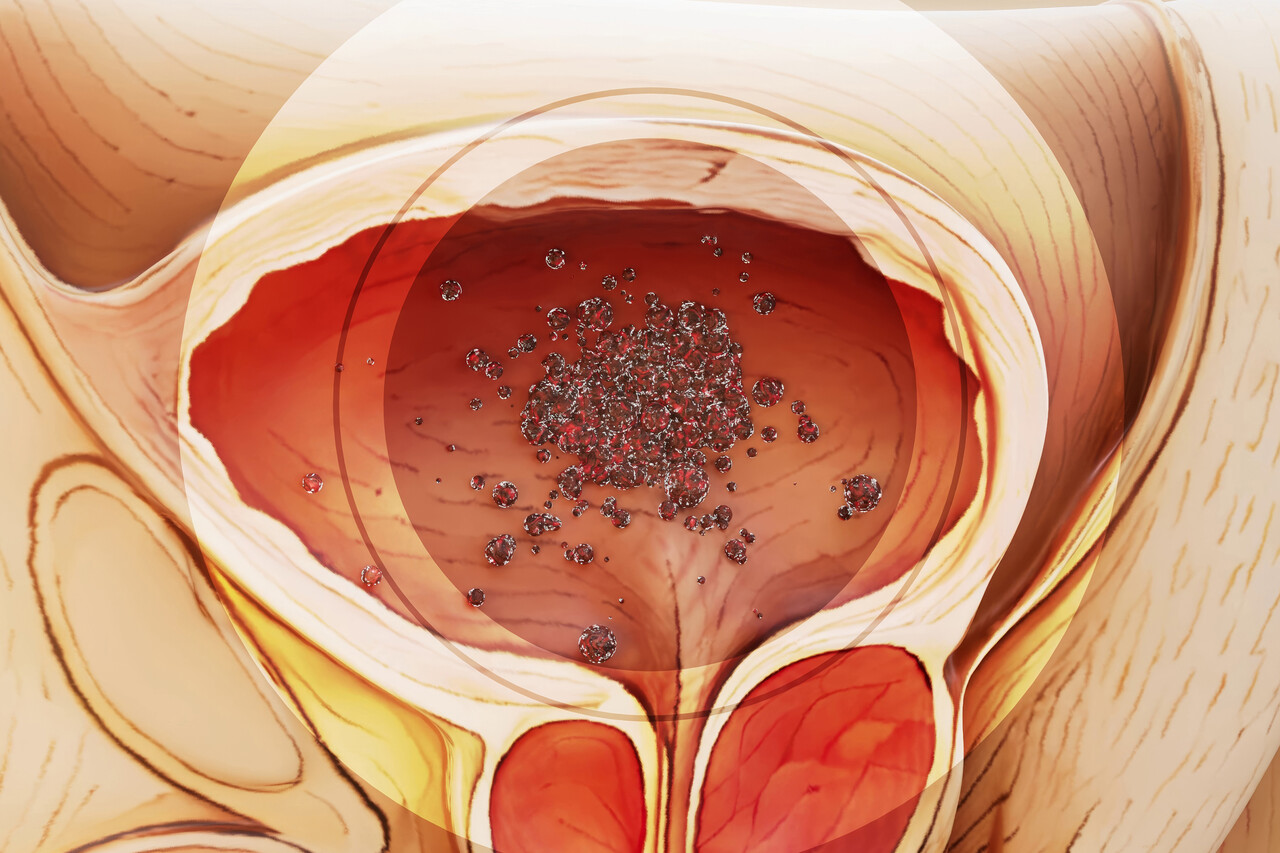

Nearly 650,000 new cases of bladder cancer are diagnosed globally each year, and despite advancements, treatment options remain limited, particularly for advanced stages. But a paradigm shift is underway. Emerging data suggests that analyzing circulating tumor DNA (ctDNA) isn’t just improving detection – it’s poised to become the central guiding force in tailoring therapies, even *before* the widespread adoption of antibody-drug conjugates (ADCs) reaches its full potential.

Traditionally, bladder cancer treatment decisions have relied on staging, histology, and performance status. Biomarkers like PD-L1 expression have offered some guidance for immunotherapy, but their predictive power is often imperfect. ctDNA analysis, however, offers a real-time, dynamic snapshot of the tumor’s genetic makeup, circulating in the bloodstream. This allows clinicians to monitor treatment response, detect minimal residual disease (MRD), and identify emerging resistance mechanisms with unprecedented sensitivity.

One of the most exciting applications of ctDNA lies in post-operative monitoring for MRD. Studies, including those highlighted by Nature and geneonline.com, demonstrate that detecting ctDNA after cystectomy (bladder removal) can predict recurrence with remarkable accuracy. This isn’t just about knowing *if* the cancer will return, but *when*. This information is critical for determining the need for adjuvant therapies – treatments given after surgery to eliminate any remaining cancer cells.

The recent interest in ADCs for bladder cancer, as reported by Oncology News Central, is undoubtedly a positive development. However, questions remain about patient selection and predicting response. Here’s where ctDNA steps in. Analyzing ctDNA before and during ADC treatment can identify patients most likely to benefit, monitor for the development of resistance mutations (like alterations in the ADC target), and potentially guide the selection of alternative therapies when resistance emerges.